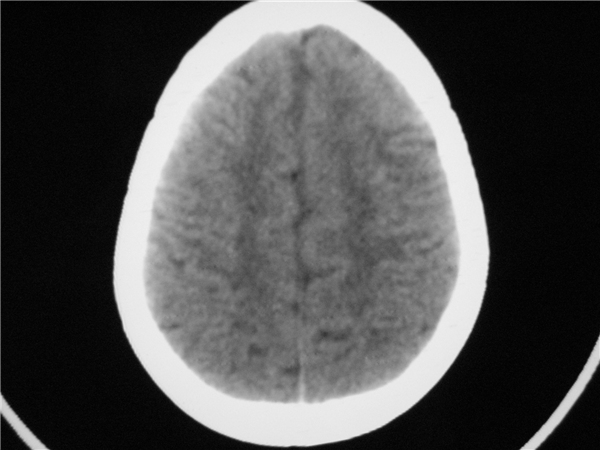

标题: PED2843: CT-23675 F 4Y 大家看看颅内有问题没。 [打印本页]

标题: PED2843: CT-23675 F 4Y 大家看看颅内有问题没。

未见明显异常。

四脑室扩大,三脑室稍扩大上移

胼胝体发育不全??

六脑室

四脑室扩大,,六脑室

颅脑ct平扫未见异常。

颅脑ct轴位平扫颅内未见明确异常。

四脑室扩大,密度降低,图像的问题?建议mr扫描。